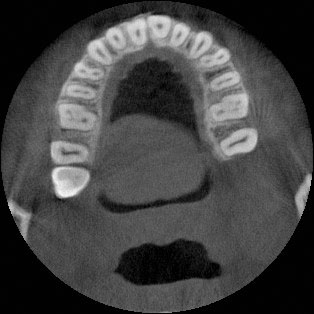

A 27-year-old female patient presented with class III malocclusion, 15 mm crowding in the upper arch, an anterior open bite, a lateral crossbite, and a total ABO score of 29. Her facial profile was straight with a retrusive maxilla, and the upper and lower incisors were retroclined. An extreme lack of midface support was also noted, and the constricted dental arches resulted in a poor smile width and dark buccal corridors. No myofunctional investigations were performed at the time, as they were initially considered unnecessary.

Adhering to the principles of Face First Orthodontics, the primary objective was to increase midface support by expanding the upper maxilla, fixing the cross bite, and aligning the teeth. Closing the open bite was a secondary objective.

Dr. Coca’s treatment plan followed the Biology First Orthodontics approach, which aims to minimize biological interventions. The treatment plan avoided extractions, stripping, TADs, corticotomy, and RPE. Given the facial requirements, a non-extraction treatment option was chosen.